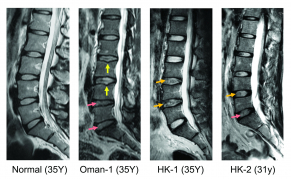

The study result shows that among different populations, LDD cases have been found a genetic variant for an enzyme with them, which is believed to have association with the development of LDD. In the Hong Kong population, the estimated frequency of the risk variant is 43% for the LDD subjects. The image illustrates the condition of patients with LDD.

The central part of the normal disc has a gel-like property that provides a cushioning effect, acting as a shock absorber as well as facilitating motion and function of the spine in daily activity. The CHST3 enzyme is essential for ensuring that the macromolecular components can function properly by keeping it hydrated. The variant form of the genes causes changes in the amount of CHST3, leading to a reduction of water in the central compartment of the disc, which is a hallmark of disc degeneration.